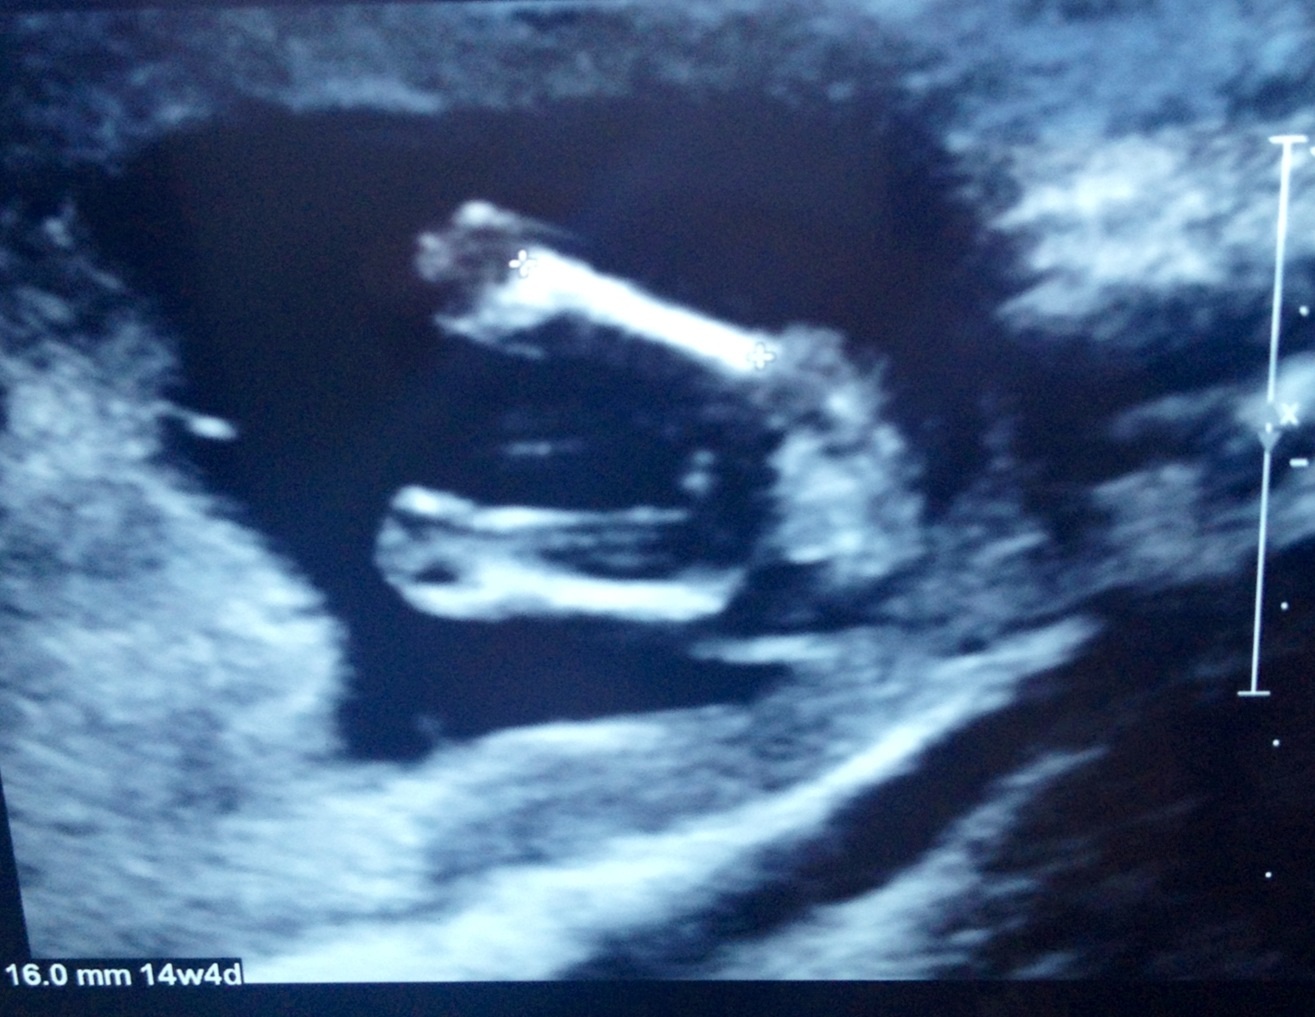

So excited and a bit in shock, but here are my GIRL pics for you all!! I still can't believe it and I'm still thinking I'm going to see a pp at the next scan!!! Good luck everyone

My confirmed girl pics at 12 weeks, 15 weeks and 17 weeks...

Attachment 13332